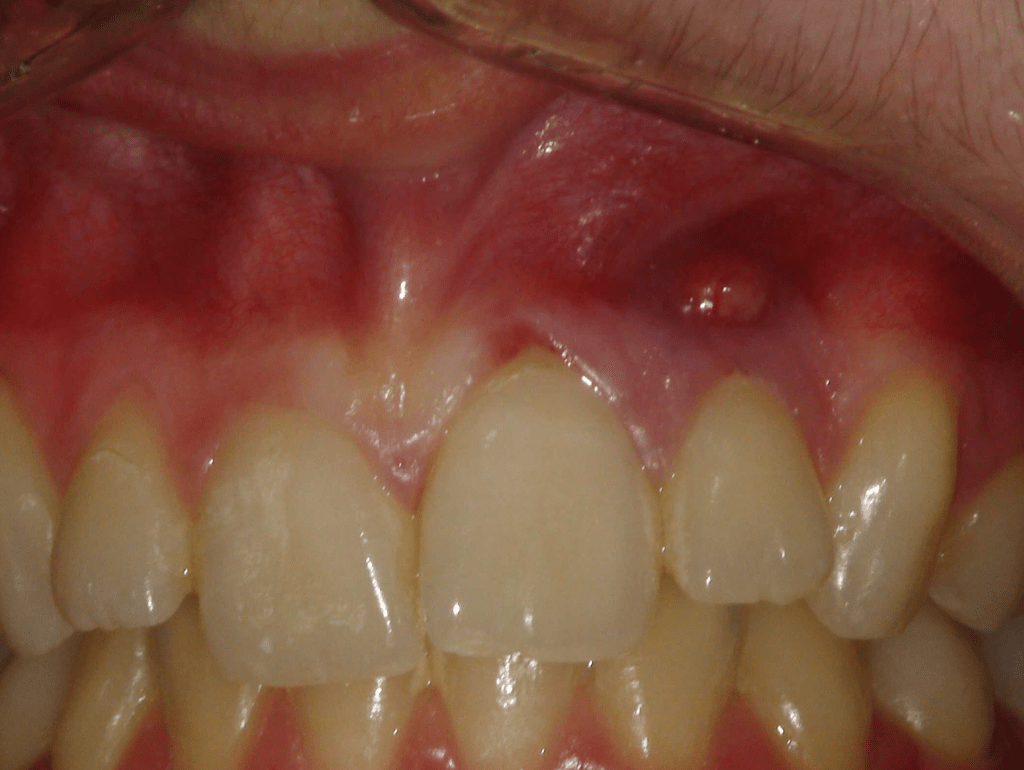

Fistula, dent in dente